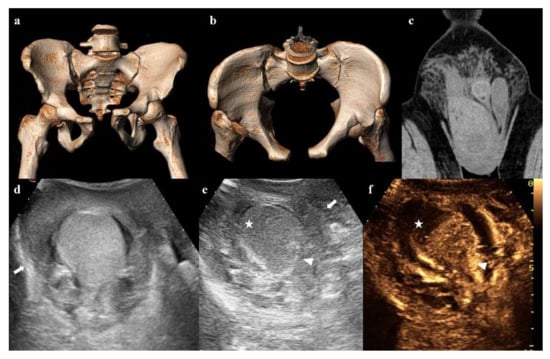

Figure 14. Three-dimensional volume-rendering CT reconstructions in AP and inlet views show an anterior–posterior compression fracture (a,b). Coronal CT image shows hematoma in the right inguinoscrotal region (c). Ultrasound shows an inhomogeneous hematoma on the extra-albuginea side (arrow in (d,e)) and a hypoechoic area in the upper part of the testis (star in (e)). Contrast-enhanced ultrasonography (CEUS) image clearly shows that the hypoechoic area is avascularized, as a hematoma (star in (f)). Ultrasound and CEUS also show the irregularity of the testicular contour (arrowhead in (e,f)). These findings are suggestive of testicular rupture.

Testicular trauma can be associated with pelvic fractures, especially in the case of motor vehicle crashes and falls from a height [66].

Ultrasound and contrast-enhanced ultrasonography (CEUS) are indispensable in the proper management of these injuries. Findings of testicular trauma are hematocele, intratesticular hematoma, and testicular rupture (Figure 14) [67,68].

Magnetic resonance (MR) has great value in the evaluation of scrotal lesions, but it is rarely available in an emergency department [67,69]. Its use may be crucial in the identification of testicular rupture when ultrasound evaluation is inconclusive [70].